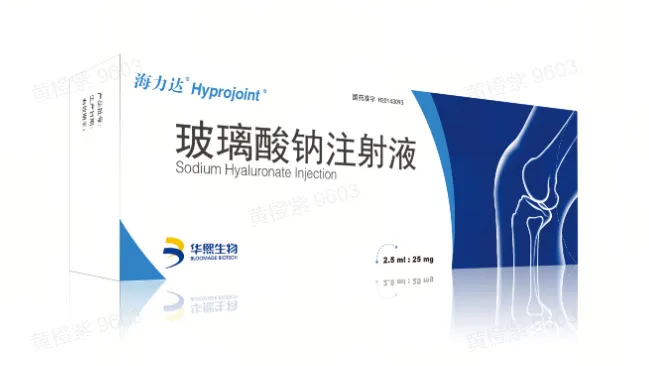

生物材料全产业链平台公司

华熙生物成立于2000年,作为一家全球领先的生物科技与生物制造企业,公司率先实现抗衰核心物质透明质酸的生物制造,市场份额常年全球第一,并以此优势为基础打开了对糖生物学和细胞生物学的前沿研究。依托公司建成的全球最大合成生物制造平台,华熙生物致力于将生命科学成果转化为应用于衰老干预、组织再生等领域的创新解决方案,目前已构建起了一个从原料到终端产品,涵盖医药、医美、营养科学和皮肤科学的整合解决方案,推出了润百颜、夸迪、米蓓尔、肌活、华熙当康等品牌。秉持“让每个生命都是鲜活的”企业使命,持续推动健康与美丽事业的发展。